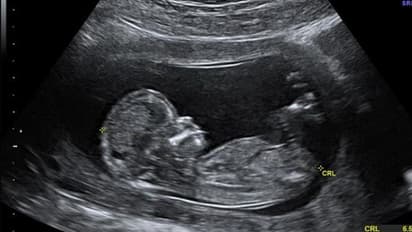

ರೋಮ್(ಡಿ.,24): ಜಗತ್ತನ್ನು ಆತಂಕಕ್ಕೆ ದೂಡುವ ವಿದ್ಯಮಾನವೊಂದರಲ್ಲಿ ಇದೇ ಮೊದಲ ಬಾರಿ ಮಾಸುಚೀಲ ಅಥವಾ ಹೊಕ್ಕುಳ ಬಳ್ಳಿ (ಪ್ಲೇಸೆಂಟಾ)ಯಲ್ಲಿ ಮೈಕ್ರೋಪ್ಲಾಸ್ಟಿಕ್ ಪತ್ತೆಯಾಗಿದೆ. ಇಟಲಿಯಲ್ಲಿ ನಡೆದ ಅಧ್ಯಯನವೊಂದರಲ್ಲಿ ಈ ಅಂಶ ಹೊರಬಿದ್ದಿದ್ದು, ಸರ್ವವ್ಯಾಪಿಯಾಗಿರುವ ಪ್ಲಾಸ್ಟಿಕ್ ಹೊಕ್ಕುಳ ಬಳ್ಳಿಗೆ ಪ್ರವೇಶಿಸಿದ್ದು ಹೇಗೆ ಎಂದು ವಿಜ್ಞಾನಿಗಳು ತಲೆಕೆಡಿಸಿಕೊಂಡಿದ್ದಾರೆ.

ಮೈಕ್ರೋಪ್ಲಾಸ್ಟಿಕ್ ಅಂದರೆ ಪ್ಲಾಸ್ಟಿಕ್ನ 5 ಮಿ.ಮೀ.ಗಿಂತ ಸಣ್ಣ ಚೂರುಗಳು. ಹೊಕ್ಕುಳಬಳ್ಳಿಯು ಭ್ರೂಣಕ್ಕೆ ಆಹಾರ, ರಕ್ತ ಹಾಗೂ ಆಮ್ಲಜನಕ ಒದಗಿಸುವ ಮತ್ತು ಗರ್ಭಕೋಶದಿಂದ ತ್ಯಾಜ್ಯವನ್ನು ಹೊರಹಾಕುವ ಕೆಲಸ ಮಾಡುತ್ತದೆ. ಇಲ್ಲಿ ಮೈಕ್ರೋಪ್ಲಾಸ್ಟಿಕ್ ಪತ್ತೆಯಾಗಿದೆ ಅಂದರೆ ಅದು ಮಗುವಿನ ದೇಹಕ್ಕೂ ಹೋಗಿರುತ್ತದೆ. ಅಂದರೆ ಈಗ ಮಕ್ಕಳು ಸಂಪೂರ್ಣವಾಗಿ ಸಾವಯವ ಪದಾರ್ಥಗಳನ್ನು ಮಾತ್ರ ದೇಹದಲ್ಲಿಟ್ಟುಕೊಂಡು ಹುಟ್ಟುತ್ತಿಲ್ಲ, ಬದಲಿಗೆ ಅಸಾವಯವ ವಸ್ತುಗಳನ್ನೂ ದೇಹದಲ್ಲಿಟ್ಟುಕೊಂಡು ಹುಟ್ಟುತ್ತಿವೆ ಎಂದು ತಜ್ಞರು ಅಭಿಪ್ರಾಯಪಟ್ಟಿದ್ದಾರೆ.

ಇಟಲಿಯಲ್ಲಿ ಹೊಕ್ಕುಳ ಬಳ್ಳಿಯನ್ನು ದಾನ ಮಾಡಲು ಮುಂದಾದ ಆರು ಮಹಿಳೆಯರ ಪೈಕಿ ನಾಲ್ಕು ಮಹಿಳೆಯರ ಹೊಕ್ಕುಳ ಬಳ್ಳಿಯಲ್ಲಿ ಮೈಕ್ರೋಪ್ಲಾಸ್ಟಿಕ್ ಪತ್ತೆಯಾಗಿದೆ. ಹೊಕ್ಕುಳ ಬಳ್ಳಿಗೆ ಪ್ಲಾಸ್ಟಿಕ್ ಹೋಗಬೇಕು ಅಂದರೆ ಅದು ಮಹಿಳೆಯ ರಕ್ತದಲ್ಲೇ ಸೇರಿರಬೇಕು. ಕೇವಲ ಹೊಟ್ಟೆಗೆ ಪ್ಲಾಸ್ಟಿಕ್ ಹೋಗಿದ್ದರೆ ಅದು ಮಲದಲ್ಲಿ ಹೊರಹೋಗುತ್ತದೆ. ಹೀಗಾಗಿ ರಕ್ತದ ಪ್ರವಾಹಕ್ಕೆ ಮೈಕ್ರೋಪ್ಲಾಸ್ಟಿಕ್ ಹೇಗೆ ಸೇರಿಕೊಂಡಿತು ಎಂಬ ಬಗ್ಗೆ ಹೆಚ್ಚಿನ ಅಧ್ಯಯನ ನಡೆಯಬೇಕಿದೆ. ಹೊಕ್ಕುಳ ಬಳ್ಳಿ ಅಥವಾ ಮಗುವಿನ ದೇಹದಲ್ಲಿ ಮೈಕ್ರೋಪ್ಲಾಸ್ಟಿಕ್ ಸೇರಿಕೊಂಡರೆ ಮುಂದೆ ಅದು ನಾನಾ ರೀತಿಯ ಅನಾರೋಗ್ಯದ ಸಮಸ್ಯೆಗಳಿಗೆ ಕಾರಣವಾಗಬಹುದು ಎಂದು ವಿಜ್ಞಾನಿಗಳು ಆತಂಕ ವ್ಯಕ್ತಪಡಿಸಿದ್ದಾರೆ.

ಮಣ್ಣಿನಲ್ಲಿ ಪ್ಲಾಸ್ಟಿಕ್ ಎಷ್ಟುವರ್ಷವಾದರೂ ಕರಗುವುದಿಲ್ಲ, ಬದಲಿಗೆ ಸಣ್ಣ ಸಣ್ಣ ಚೂರಾಗುತ್ತದೆ. ಅದು ನೀರು, ಆಹಾರ, ಸಮುದ್ರ ಜೀವಿಗಳು, ಪ್ರಾಣಿ ಹಾಗೂ ಮನುಷ್ಯನ ದೇಹ ಸೇರಿ ಸಾಕಷ್ಟುಸಮಸ್ಯೆ ಉಂಟುಮಾಡುತ್ತಿದೆ. ಈಗ ಅದು ಹೊಕ್ಕುಳ ಬಳ್ಳಿಯಲ್ಲೂ ಪತ್ತೆಯಾಗಿರುವುದರಿಂದ ಪ್ಲಾಸ್ಟಿಕ್ನ ಮಾರಕತೆ ಇನ್ನೊಂದು ಮಜಲಿಗೆ ಏರಿದಂತಾಗಿದೆ ಎಂದು ವಿಜ್ಞಾನಿಗಳು ಆತಂಕ ವ್ಯಕ್ತಪಡಿಸಿದ್ದಾರೆ.